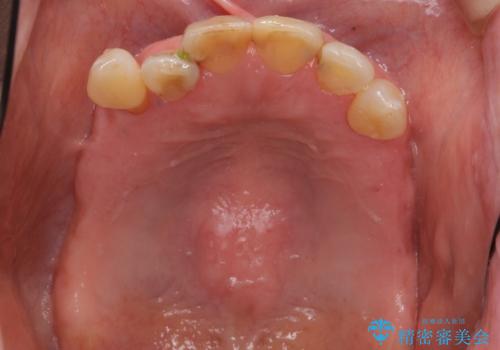

- 上の奥歯がないまま長年過ごしていたら前歯もぐらぐらしてきてしまったことを主訴に来院された患者様です。

奥歯の咬み合わせがないことにより前歯に負担がかかり動揺が出ていました。

上の前歯は動揺を抑え、入れ歯の着脱にも耐えうるように被せ物を連結させることにしました。